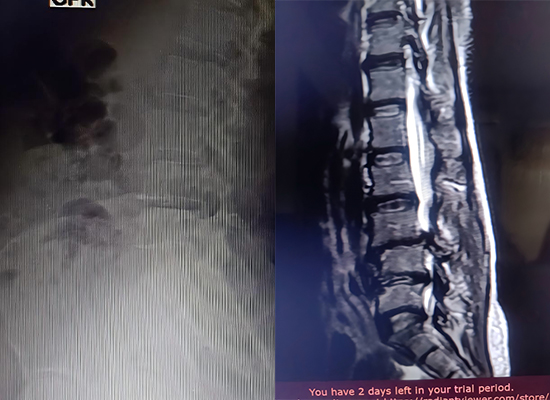

This case presents a successful lumbar spine surgery performed in Nigeria using TLIF PEEK cages combined with a spinal pedicle screw system supplied by CZMEDITECH. The procedure achieved effective decompression, interbody fusion, and stable fixation, demonstrating reliable clinical performance in emerging markets.

L3–L5 decompressive laminectomy was performed, followed by TLIF cage insertion at L3/4 and L4/5 levels, with pedicle screw fixation.

Postoperative imaging showing stable fixation using pedicle screw system

Stable fixation achieved

No complications

Early ambulation

Good recovery